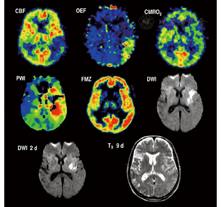

MR扩散和灌注成像能够区别梗死灶的中心和缺血半暗带。弥散加权成像(diffusion-weighted imaging,DWI)在早期显示的病灶为梗死灶核心,其邻近组织在灌注加权成像(perfusion-weighted imaging,PWI)上表现为低灌注。因此,PWI表现为低灌注而无明确界限的脑区(PWI-DWI不匹配区)定义为缺血半暗带[56],这种以显像不匹配区域来表示缺血半暗带的方法,DWI病灶几乎都为梗死组织,但PWI的数据采集并不完全准确,用于估算灌注的参数也是可变的且不完全正确。因此,脑灌注显示的病灶大小存在显著不同,且通常测量值偏大。达峰时间延迟4~6 s,能识别低灌注和正常灌注的组织,但会高估脑灌注减少但仍然存活组织的容积[57],因此在PWI-DWI上不匹配的容积(即缺血半暗带)与PET显像中显示的低灌注容积并不完全匹配(图4)。PWI参数与H215O PET血流量值的验证研究[58]可校正分类的准确性,但潜在可逆性、缺血最大容积、CBF和达峰值面积时间不能校正。

急性缺血性脑卒中的疗效监测也是建立在显像研究的基础上,缺血半暗带再灌注后可改善神经功能的损害(图5):患者接受rtPA治疗后的再灌注量与对照组相比显著增加[64]。在脑卒中发病后的3 h内,H215O PET CBF显像能够确定再灌注可修复组织的容积,并与梗死3周后MRI的梗死容积对比[65]。最初缺血的区域(即血流量低于阈值12 ml·100 g-1·min-1)再灌注后血灌注量接近正常水平,并预测在3周内临床症状得到明显改善。在一个12例的小样本研究中,灌注量低于脑卒中临界值的灰质,仅22.7%在溶栓治疗后会发生坏死,这意味着有很大一部分缺血组织再灌注治疗后仍可修复。另一个11例患者的PET研究[66]发现,只有当11C-氟马西尼在皮质摄取不减少或不低于白质平均摄取值的3.4倍时,缺血组织的再灌注才有效。这种神经元完整性的标志物可作为不适宜接受治疗的不可逆损伤组织的一个指标。